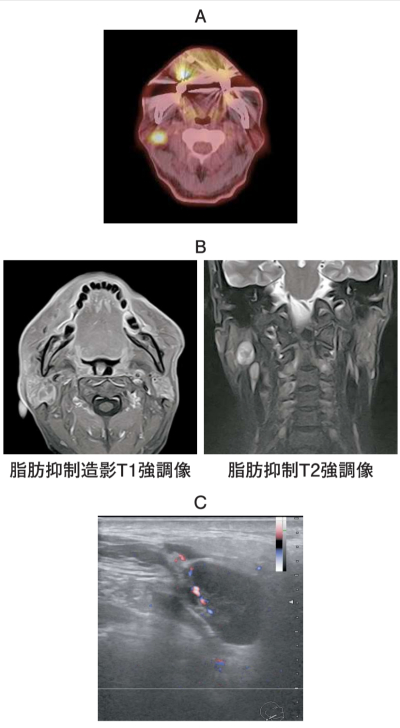

65 歳の男性。頸部の腫脹を主訴として来院した。右側耳介下部に無痛性の腫脹を認める。初診時の PET/CT、MRI 脂肪抑制造影 T1 強調像と脂肪抑制 T2 強調像、ドプラ超音波横断像及び生検時の H-E 染色病理組織像を別に示す。

診断名はどれか。1つ選べ。

a. 血管腫

b. 神経鞘腫

c. 多形腺腫

d. Warthin 腫瘍

e. リンパ節転移